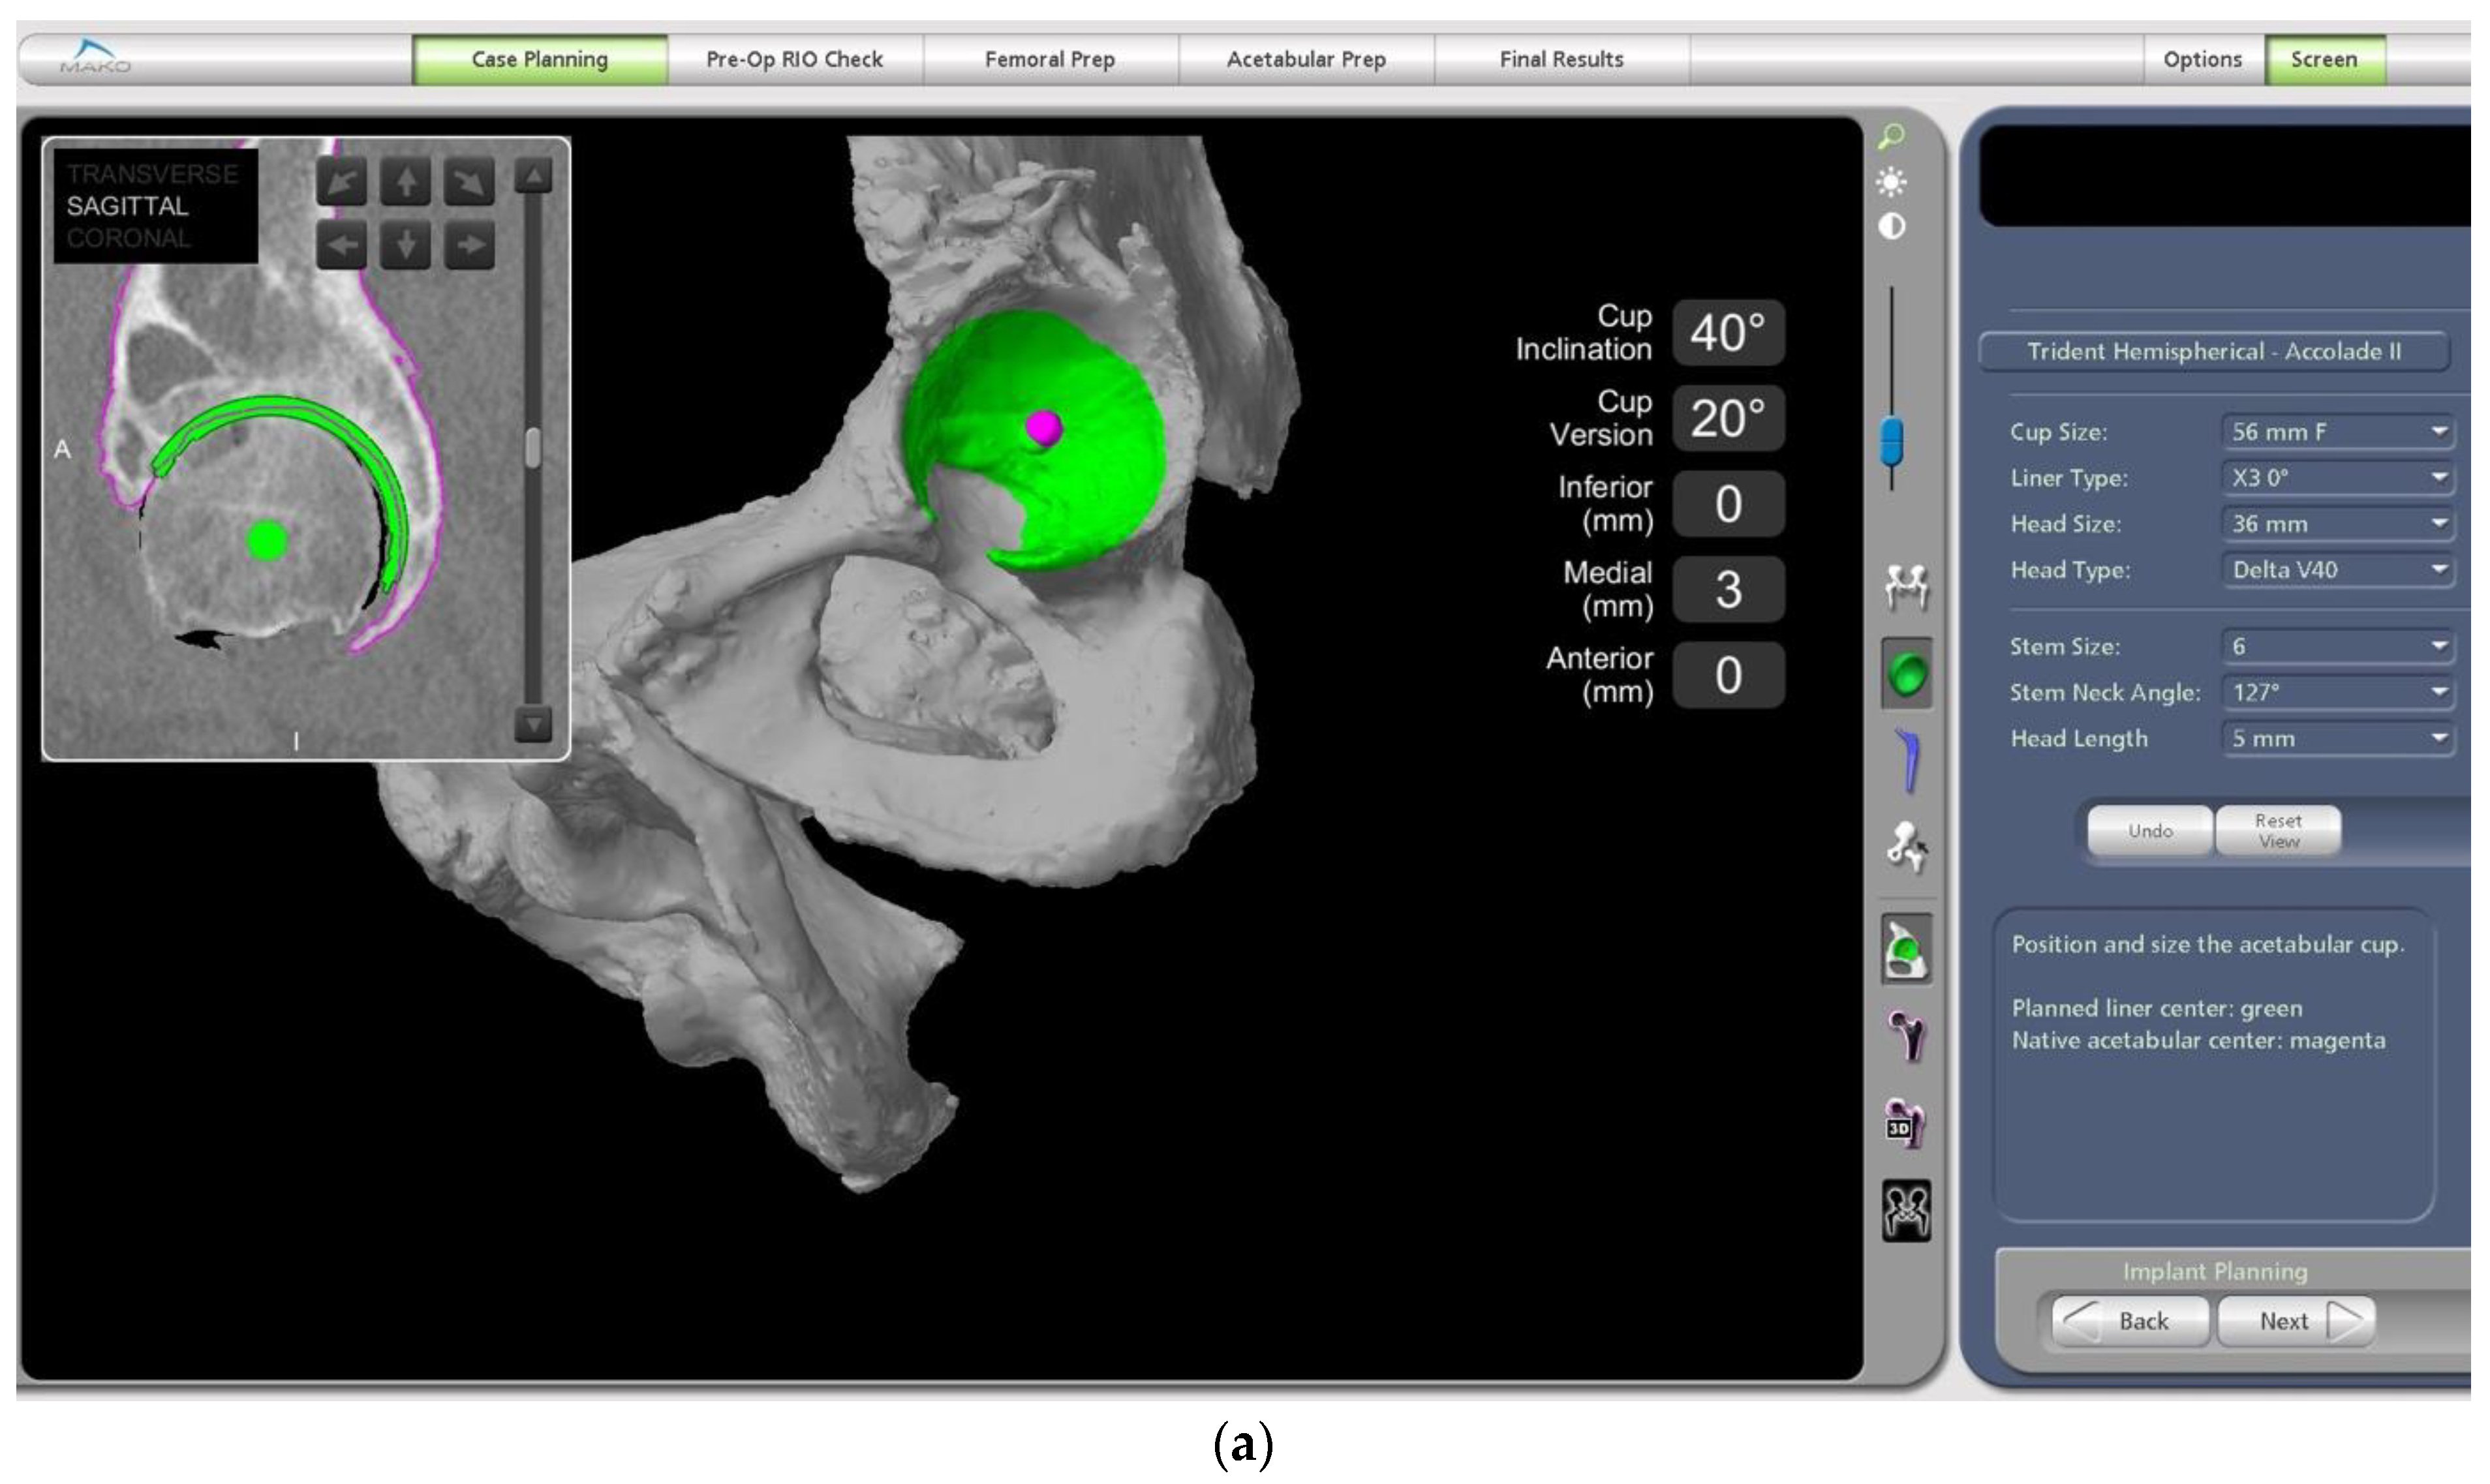

- The difference in sacral slope between standing and sitting radiographs was noted to be 6 degrees. According to the Stefl classification, this is stuck sitting, as the sacral tilt does not tilt anteriorly beyond 30 degrees with standing, indicating a high-risk patient (Figure 6a–c).

- In this case, the native femoral retroversion (−6 degrees) posed a challenge in avoiding impingement (Figure 7). Upon assessing VROM, bone-on-bone and implant-on-implant impingement in deep flexion were noted (Figure 8). Using the robotic software, the planned femoral version was corrected to +16 in the femoral broach (Figure 9a,b).

- The robotic software also enables preoperative and intraoperative visualisation of the anticipated postoperative X-rays accounting for any changes to the plan. In addition, the software allows for calculation of changes to the leg length offset compared to the preoperative and contralateral hips. In this case, the leg length was 1 mm longer compared to the opposite hip, and the combined offset was 6 mm increased compared to that preoperatively (Figure 12a,b).